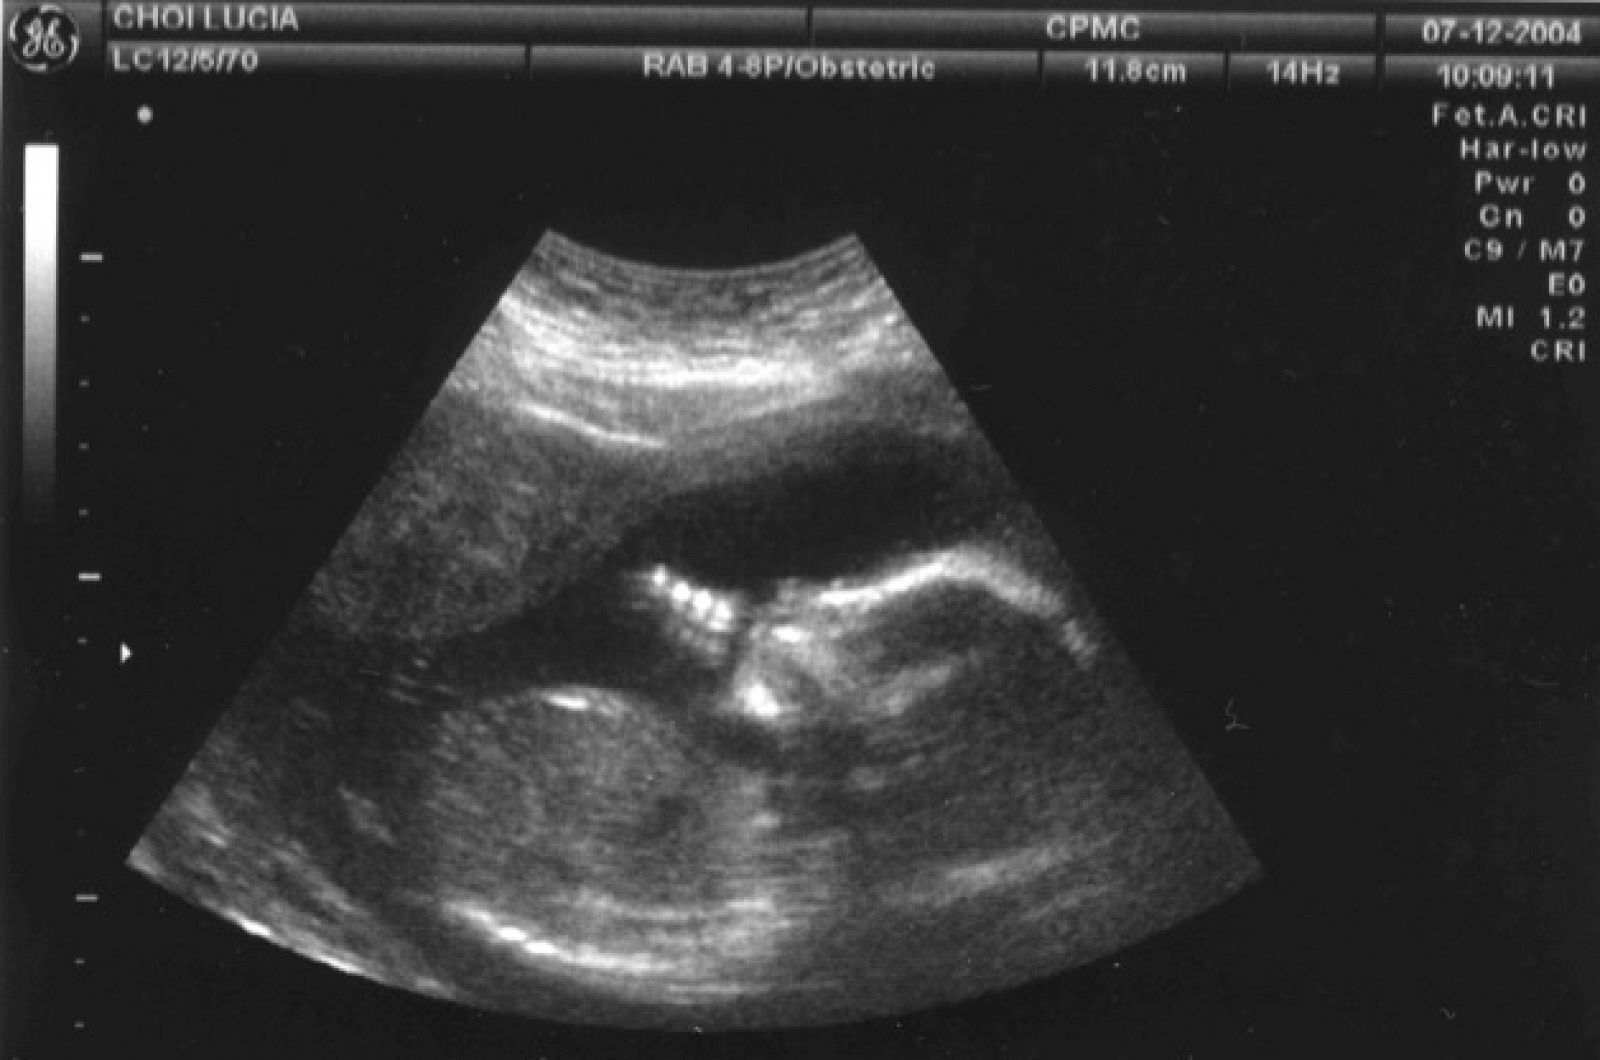

Cuando no existe la urgencia de conocer si el bebé sufrirá alguna enfermedad genética se recurre a las ecografías para saber el sexo.

En ese caso el género se puede averiguar en una de las ecografías periódicas que el ginecólogo realiza a la mujer, que se producen en las semanas 12, 20 y 36 de embarazo.